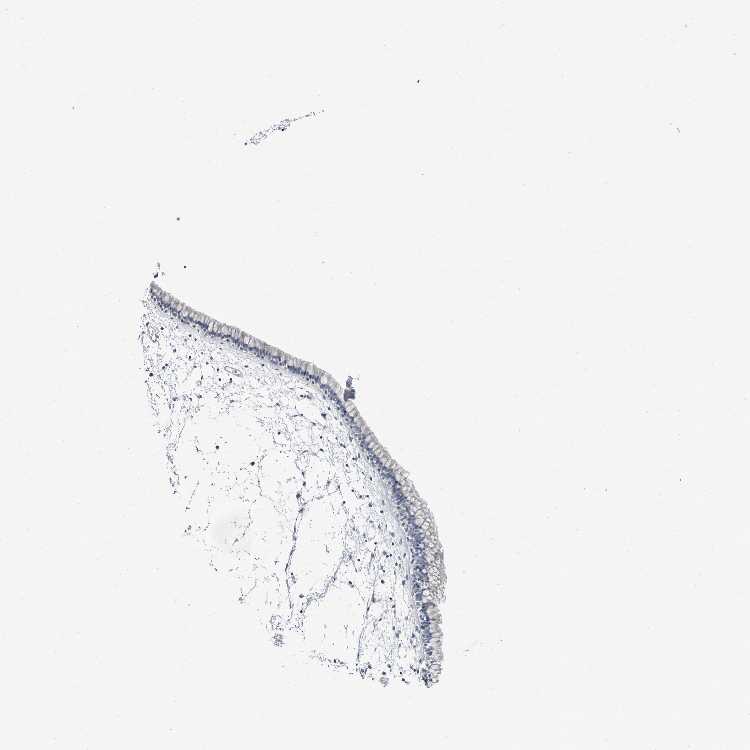

TISSUE PRIMARY DATA NASOPHARYNX Show tissue menu

NASOPHARYNX - Antibody stainingi

Antibody staining in the annotated cell types in the current human tissue is reported as not detected, low, medium, or high, based on conventional immunohistochemistry profiling in selected tissues. This score is based on the combination of the staining intensity and fraction of stained cells.

Each image is clickable and will lead to virtual microscopy that enables deeper exploration of all samples and also displays staining intensity scores, fraction scores and subcellular localization as well as patient and tissue information for each sample.

Antibody HPA026900Antibody CAB005597

Respiratory epithelial cells LowNot detected